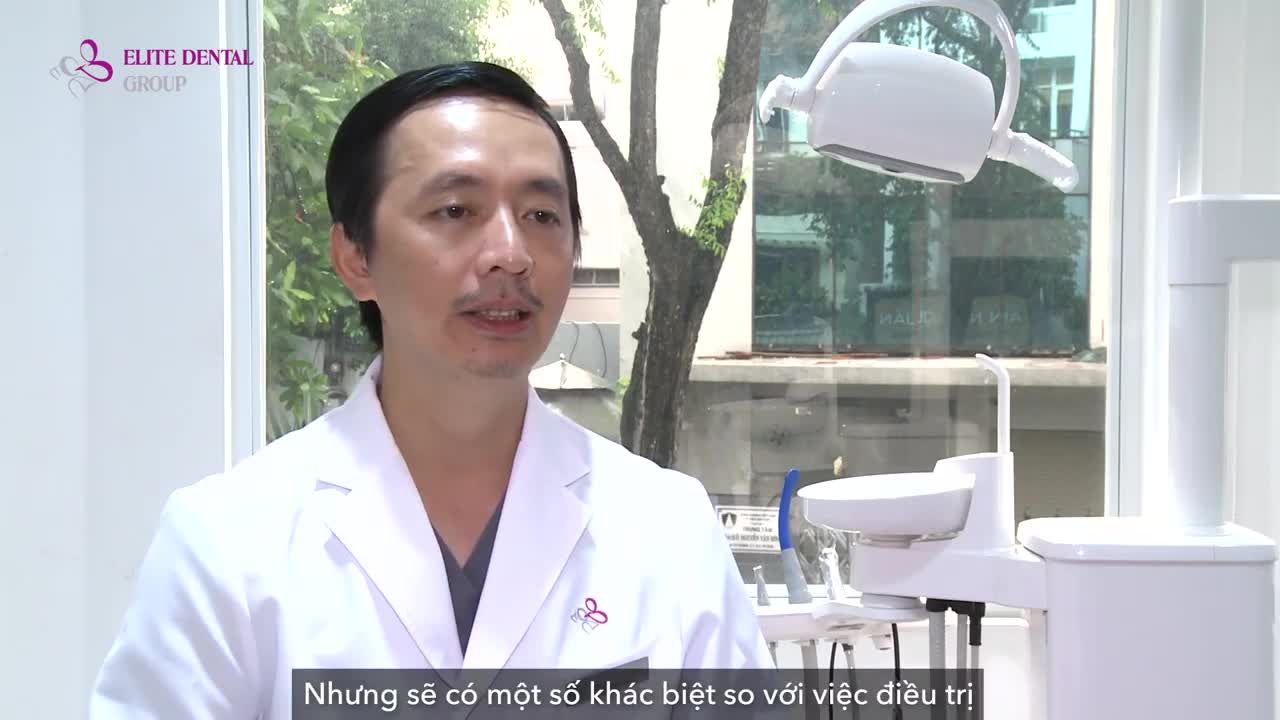

Tốt nghiệp loại giỏi trường Đại học Y Dược TP.HCM

Lấy bằng tiến sĩ và có thời gian thực hành tại Pháp.

Diplomate ICOI (International Congress of Oral Implantologists)

Diễn giả được đề cử ITI (International Team of Implantology)

Chủ tịch ITI VN ( International Team of Implantology)

Diplome Implant tại Marseille, Pháp

Tổng thư ký Hội cấy ghép nha khoa Tp Hồ Chí Minh (HSDI)

Bác sĩ trưởng khoa tại nha khoa Elite